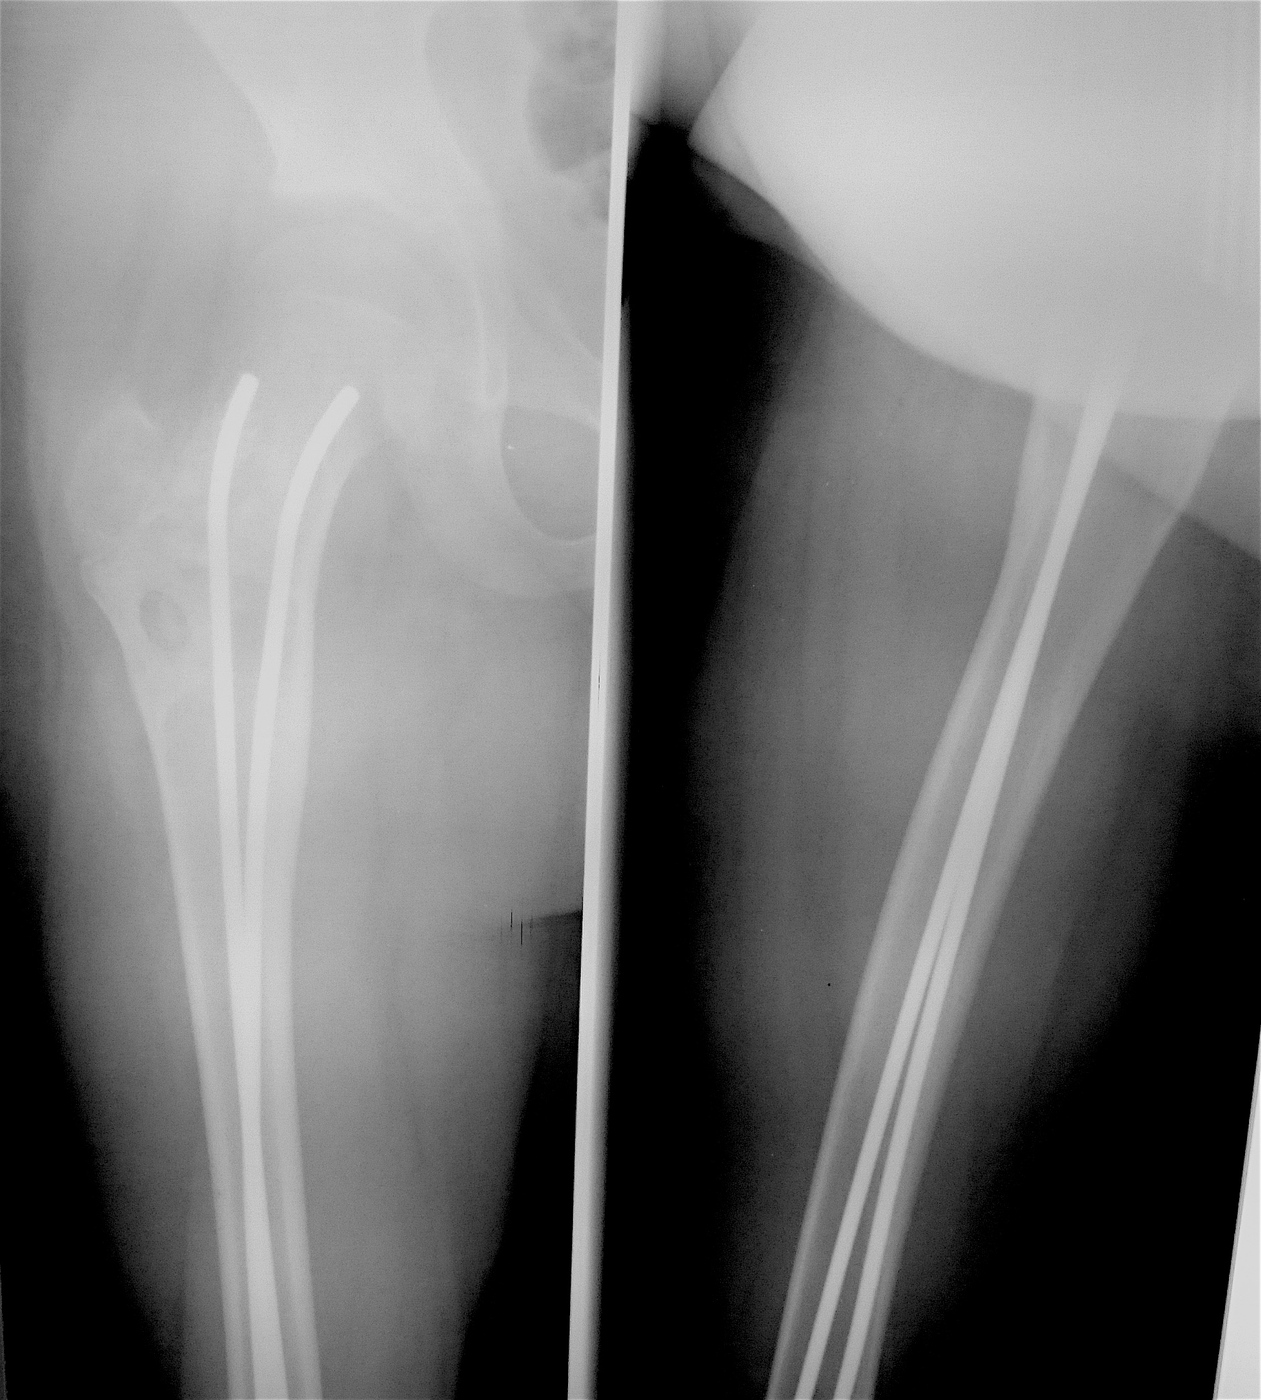

Выполнена резекция с аллопластикой губчатыми и кортикальными биоимплантатами "Лиопласт".